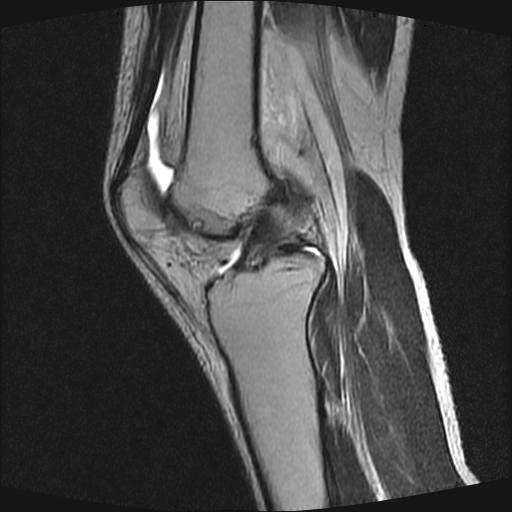

40岁男性,右膝关节外伤,x光平片示,髁间隆突撕脱骨折。

1、前交叉韧带撕裂;

前交叉韧带撕裂,关节腔积液.

半月板1-2级损伤   前交叉韧带撕裂伤   关节腔少量积液  诸骨未见新鲜外伤性改变

还有:

髁间隆突撕脱骨折;内侧副韧带损伤。

前交叉韧带撕裂,关节腔积液,支持!

2、前交叉韧带撕裂;

内侧副韧带撕裂及关节腔积液是肯定的,但是前交叉撕裂确定吗?会不会有容积效应的因素,因为前一张前交叉显示清楚,连续性良好,且较光滑。请问楼主有关节镜支持吗?我们医院也经常有这样的患者,但苦于没有关节镜,而无法对照、证实(除非完全断裂),出现了不同的诊断结果只能毫无意义的争论。

1、前交叉韧、内侧副韧带撕裂;

2、外侧半月板后角撕裂;

3、关节腔积液。4、髁间脊撕脱骨折。

除了关节积液外并无韧带撕裂,acl胫侧附着点有2束,正常情况下脂肪信号。此病例应加做压脂像以便观察是否有骨损伤。